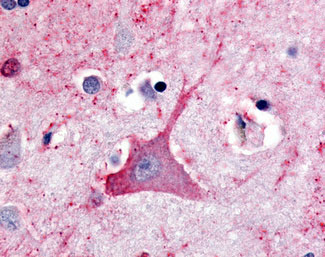

Anti-TRH Receptor antibody AMM08320G IHC of human brain, neuron. |